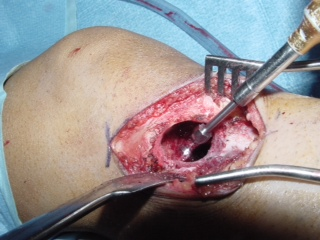

• Curettage (Fig. 10 & 11)

• Usually initial treatment

• Adjuvant therapy is recommended to reduce the recurrence rate. Cryotherapy for benign aggressive tumors has excellent results reducing the recurrence rate to approximately 3 to 5 %.